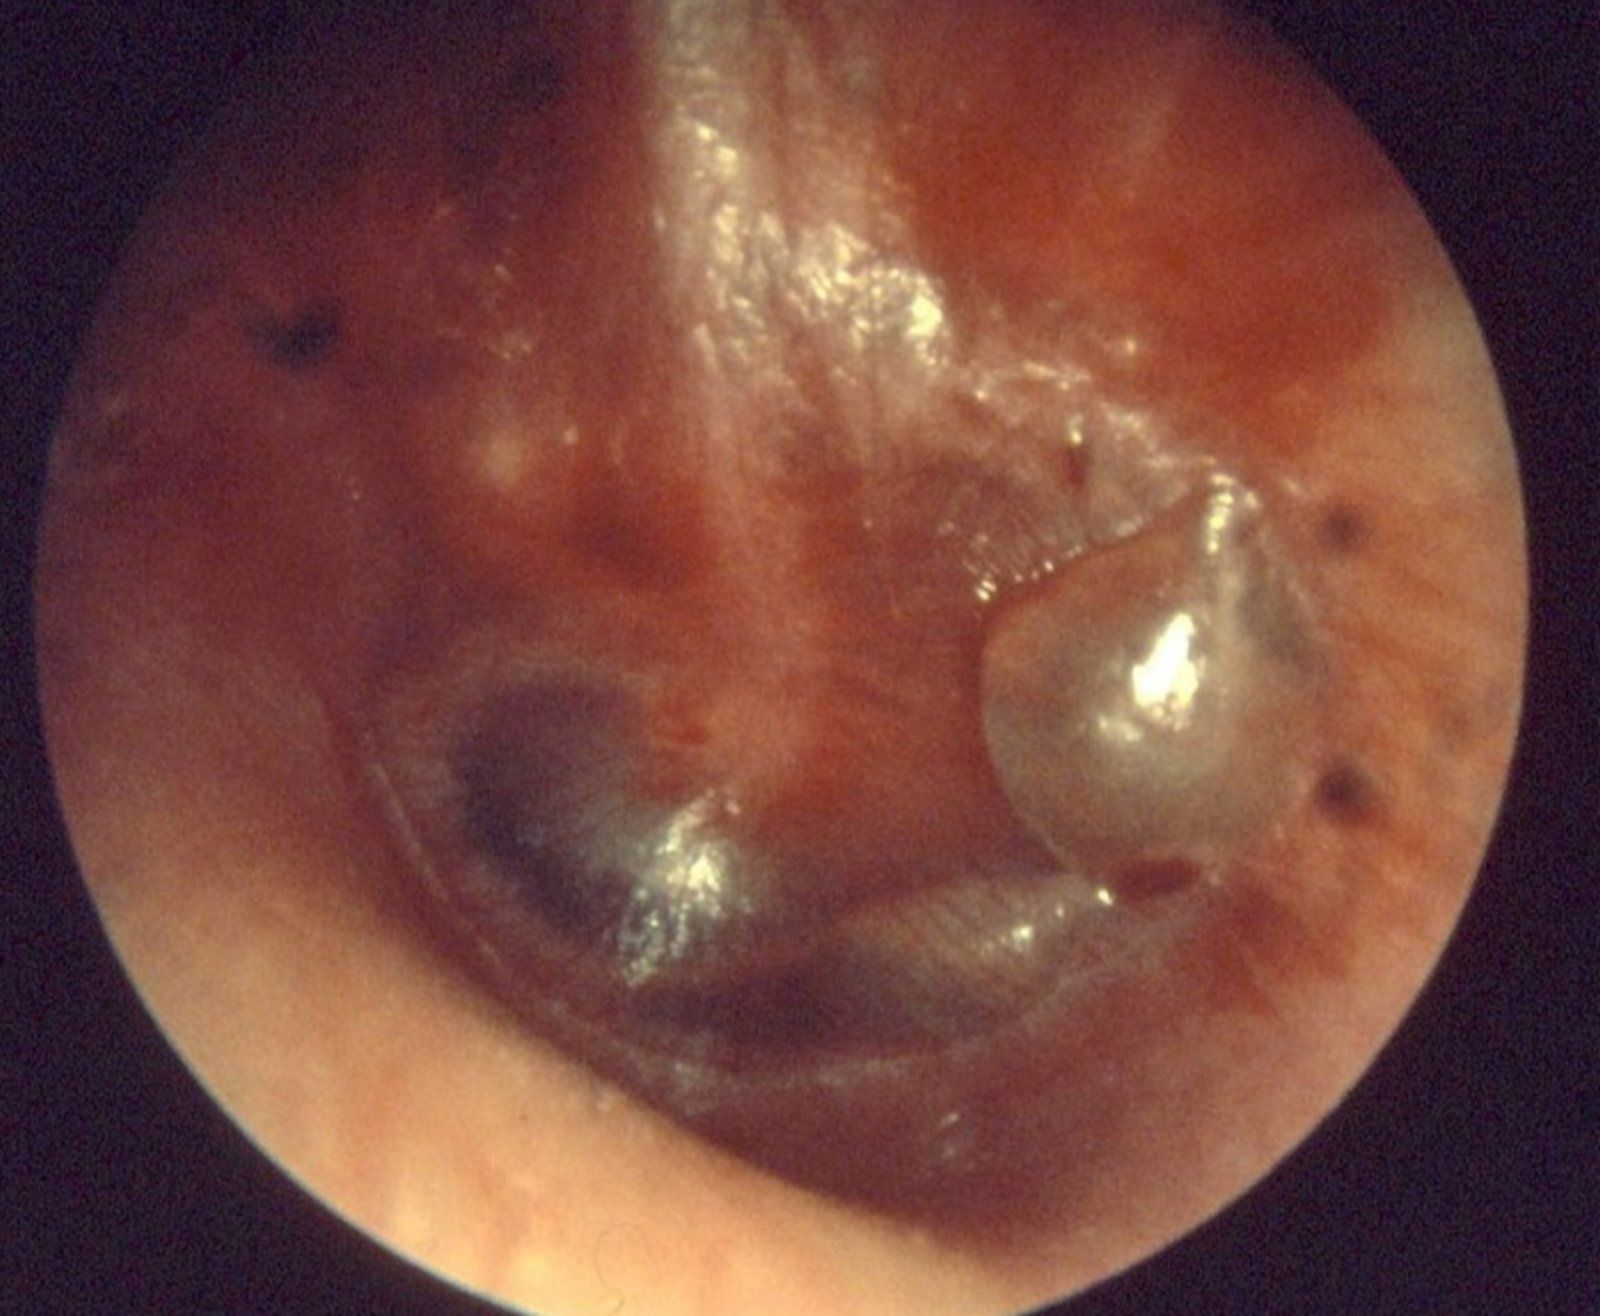

Το υγρό στο αυτί φαίνεται εύκολα με την συνηθισμένη και απλή ωτοσκόπηση που μπορεί να κάνει από ένας ανειδίκευτος ιατρός έως και ο ειδικός πού είναι ο ωτορινολαρυγγολόγος.

- Με ωτοσκόπηση. Μέσω της διαυγούς τυμπανικής μεμβράνης φαίνεται το υγρό στο μέσο ους είτε δημιουργώντας επίπεδο, είτε αλλοιώνοντας τα ωτοσκοπικά χαρακτηριστικά.